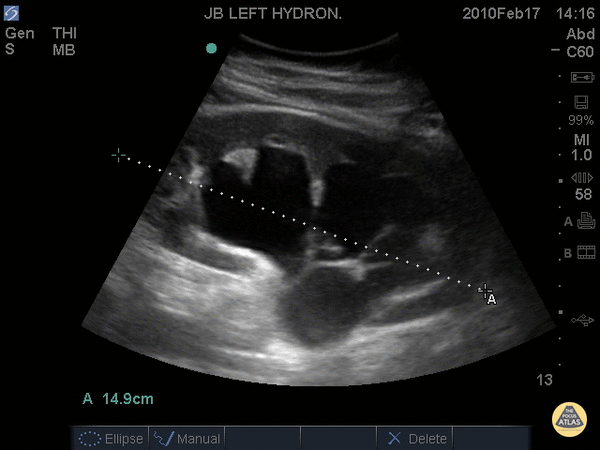

Renal/GU - Severe Hydronephrosis

14.9cm long axis In this patient with severe hydronephrosis, there is gross dilation of both the renal pelvis and calyces, which are ballooned. The cortex of the kidney has atrophied and is very thin. Dr. Justin Bowra et al.